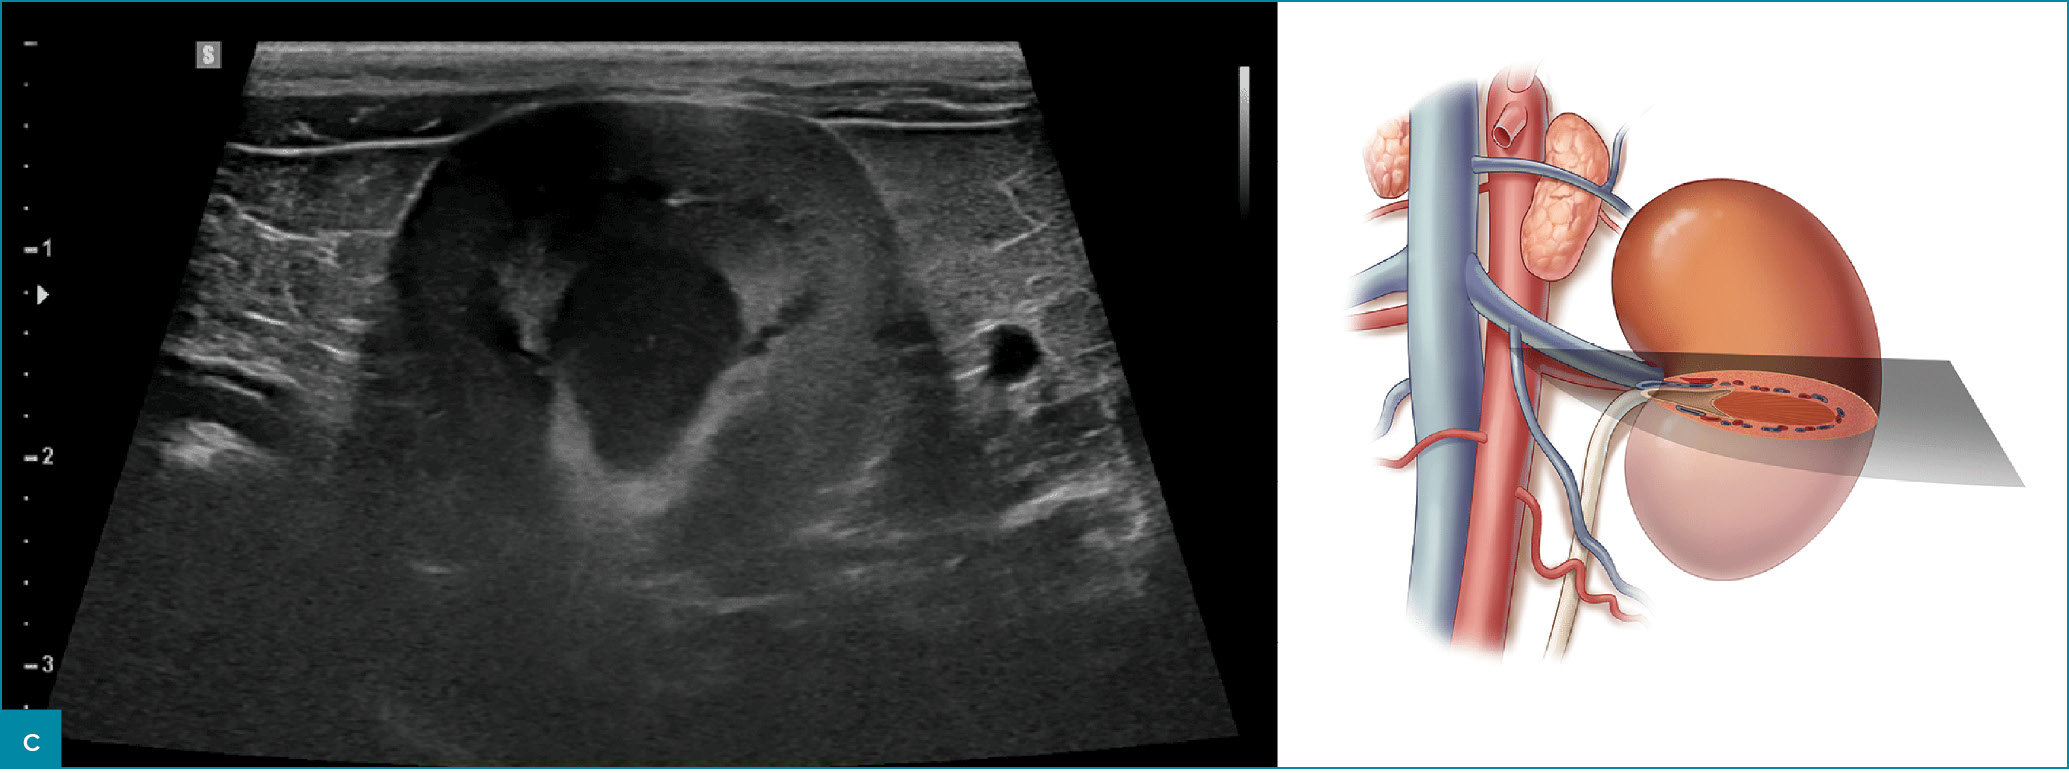

Prawidłowy obraz ultrasonograficzny nerek został szczegółowo omówiony w innych źródłach,7 a poniższy artykuł koncentruje się na przewlekłej chorobie nerek u kotów i psów. Nerki powinny być obrazowane w trzech projekcjach – strzałkowej, dogrzbietowej i poprzecznej (ryc. 1).7 U psów, zwłaszcza małych ras, opisano obecność hiperechogenicznego zewnętrznego pasma rdzeniowego, które obserwuje się z umiarkowaną częstością u pacjentów bez stwierdzonej choroby nerek (ryc. 2).8 U kotów kora nerek może być jednorodnie silnie hiperechogeniczna ze zwiększonym w następstwie zróżnicowaniem korowo-rdzeniowym wtórnym do lipidozy kanalików bliższych (ryc. 3).9 Odkładanie się tłuszczu w kanalikach nerkowych jest konsekwencją otyłości bez jednoczesnego upośledzenia czynności nerek.10 Dodatkowo rutynowo obserwuje się zależny od kąta badania artefaktowy wzrost hiperechogeniczności kory i rdzenia nerek, wtórny do anizotropii, w obszarach, w których kanaliki nerkowe ułożone są prostopadle do płaszczyzny fali ultradźwiękowej. Na przykład podczas obrazowania nerki w projekcji strzałkowej echogeniczność biegunów doczaszkowego i doogonowego będzie ogniskowo i artefaktowo zwiększona (ryc. 4).11 Z doświadczenia autorów wynika, że łagodna nieregularność brzegów nerek, szczególnie u kotów, może być obserwowana w miejscach, gdzie naczynia nerkowe przebiegają wzdłuż torebki nerkowej, i nie powinna być błędnie interpretowana jako zmiana zwyrodnieniowa (ryc. 5). W lokalizowaniu tych naczyń użyteczna jest ultrasonografia dopplerowska kodowana kolorem lub w trybie mocy.

Ryc. 1. Obrazy ultrasonograficzne prawidłowej nerki kota w projekcji: a) strzałkowej, b) dogrzbietowej oraz c) poprzecznej. Towarzyszące ilustracje przedstawiają przebieg płaszczyzn obrazowania.